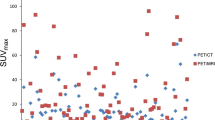

As reflected by SUVmax, collectively, [89Zr]Zr-PSMA-617 uptake (Fig. 4A) and changes in that variable over time (Fig. 4B) distinctly differed between the 6 previously-indeterminate lesions that were classified as positive on [89Zr]Zr-PSMA-617 PET/CT versus their 14 counterparts that were classified as negative. In the positive lesions, radiotracer uptake rose markedly from the 1-hr to the 24-hr scan, and then essentially plateaued at a high level through 48 h post-injection. In the negative lesions, the already very low degree of [89Zr]Zr-PSMA-617 uptake at 1

[89Zr]Zr-PSMA-617 PET variables by scan time and their relative changes over time of [68Ga]Ga-PSMA-11-indeterminate lesions visually classified as positive (n = 6 lesions) versus negative (n = 14 lesions) on [89Zr]Zr-PSMA-617 PET/CT. (A) SUVmax, (B) ∆SUVrel, (C) TLR, and (D) ∆TLRrel. ∆SUVrel, relative change in SUVmax; ∆TLRrel, relative change in TLR

hr post-injection declined in the subsequent two measurements, or the lesions did not show any clear radiotracer uptake. Additionally, TLR, a marker of lesional contrast, was markedly higher in the [89Zr]Zr-PSMA-617-positive lesions than in the [89Zr]Zr-PSMA-617-negative lesions at 24 and 48 h (Fig. 4C). Furthermore, in distinction with findings in the negative lesions, TLR increased continuously over time in the positive lesions (Fig. 4D).

[89Zr]Zr-PSMA-617 PET/CT also identified altogether 11 lesions suspicious for prostate cancer that had not been visualized at all on [68Ga]Ga-PSMA-11 PET/CT (Table 2; representative images in Fig. 5, left column). Of the newly-discovered suspicious lesions, 3 were presumed to be local recurrences, and 8, lymph node metastases. Altogether 7/15 patients (47%) had lesions newly found on [89Zr]Zr-PSMA-617 PET/CT. Every lesion that was positive on [68Ga]Ga-PSMA-11 PET/CT also was clearly seen on the [89Zr]Zr-PSMA-617 scans (representative images in Fig. 5, right column). Figure 6 shows the SUVmax and TLR of the [89Zr]Zr-PSMA-617 PET/CT of these lesions, which were already suspicious on the [68Ga]Ga-PSMA-11 PET/CT. The kinetics of these parameters were similar to those of the [68Ga]Ga-PSMA-11 indeterminate lesions, which were classified as positive by [89Zr]Zr-PSMA-617 PET/CT.

Second, negative and positive lesions showed distinctly different patterns of [89Zr]Zr-PSMA-617 kinetics. This observation was reflected by lesional radiotracer uptake, represented by SUVmax, and by lesional contrast, represented by TLR, as well as by patterns of change in these variables over the 1 to 48 h post-injection. The PET kinetics of the [68Ga]Ga-PSMA-11 indeterminate lesions, which were classified as positive by [89Zr]Zr-PSMA-617 PET/CT were similar to those of the clearly suspicious lesions on [68Ga]Ga-PSMA-11, strengthening the assumption of correct classification by [89Zr]Zr-PSMA-617 PET/CT.